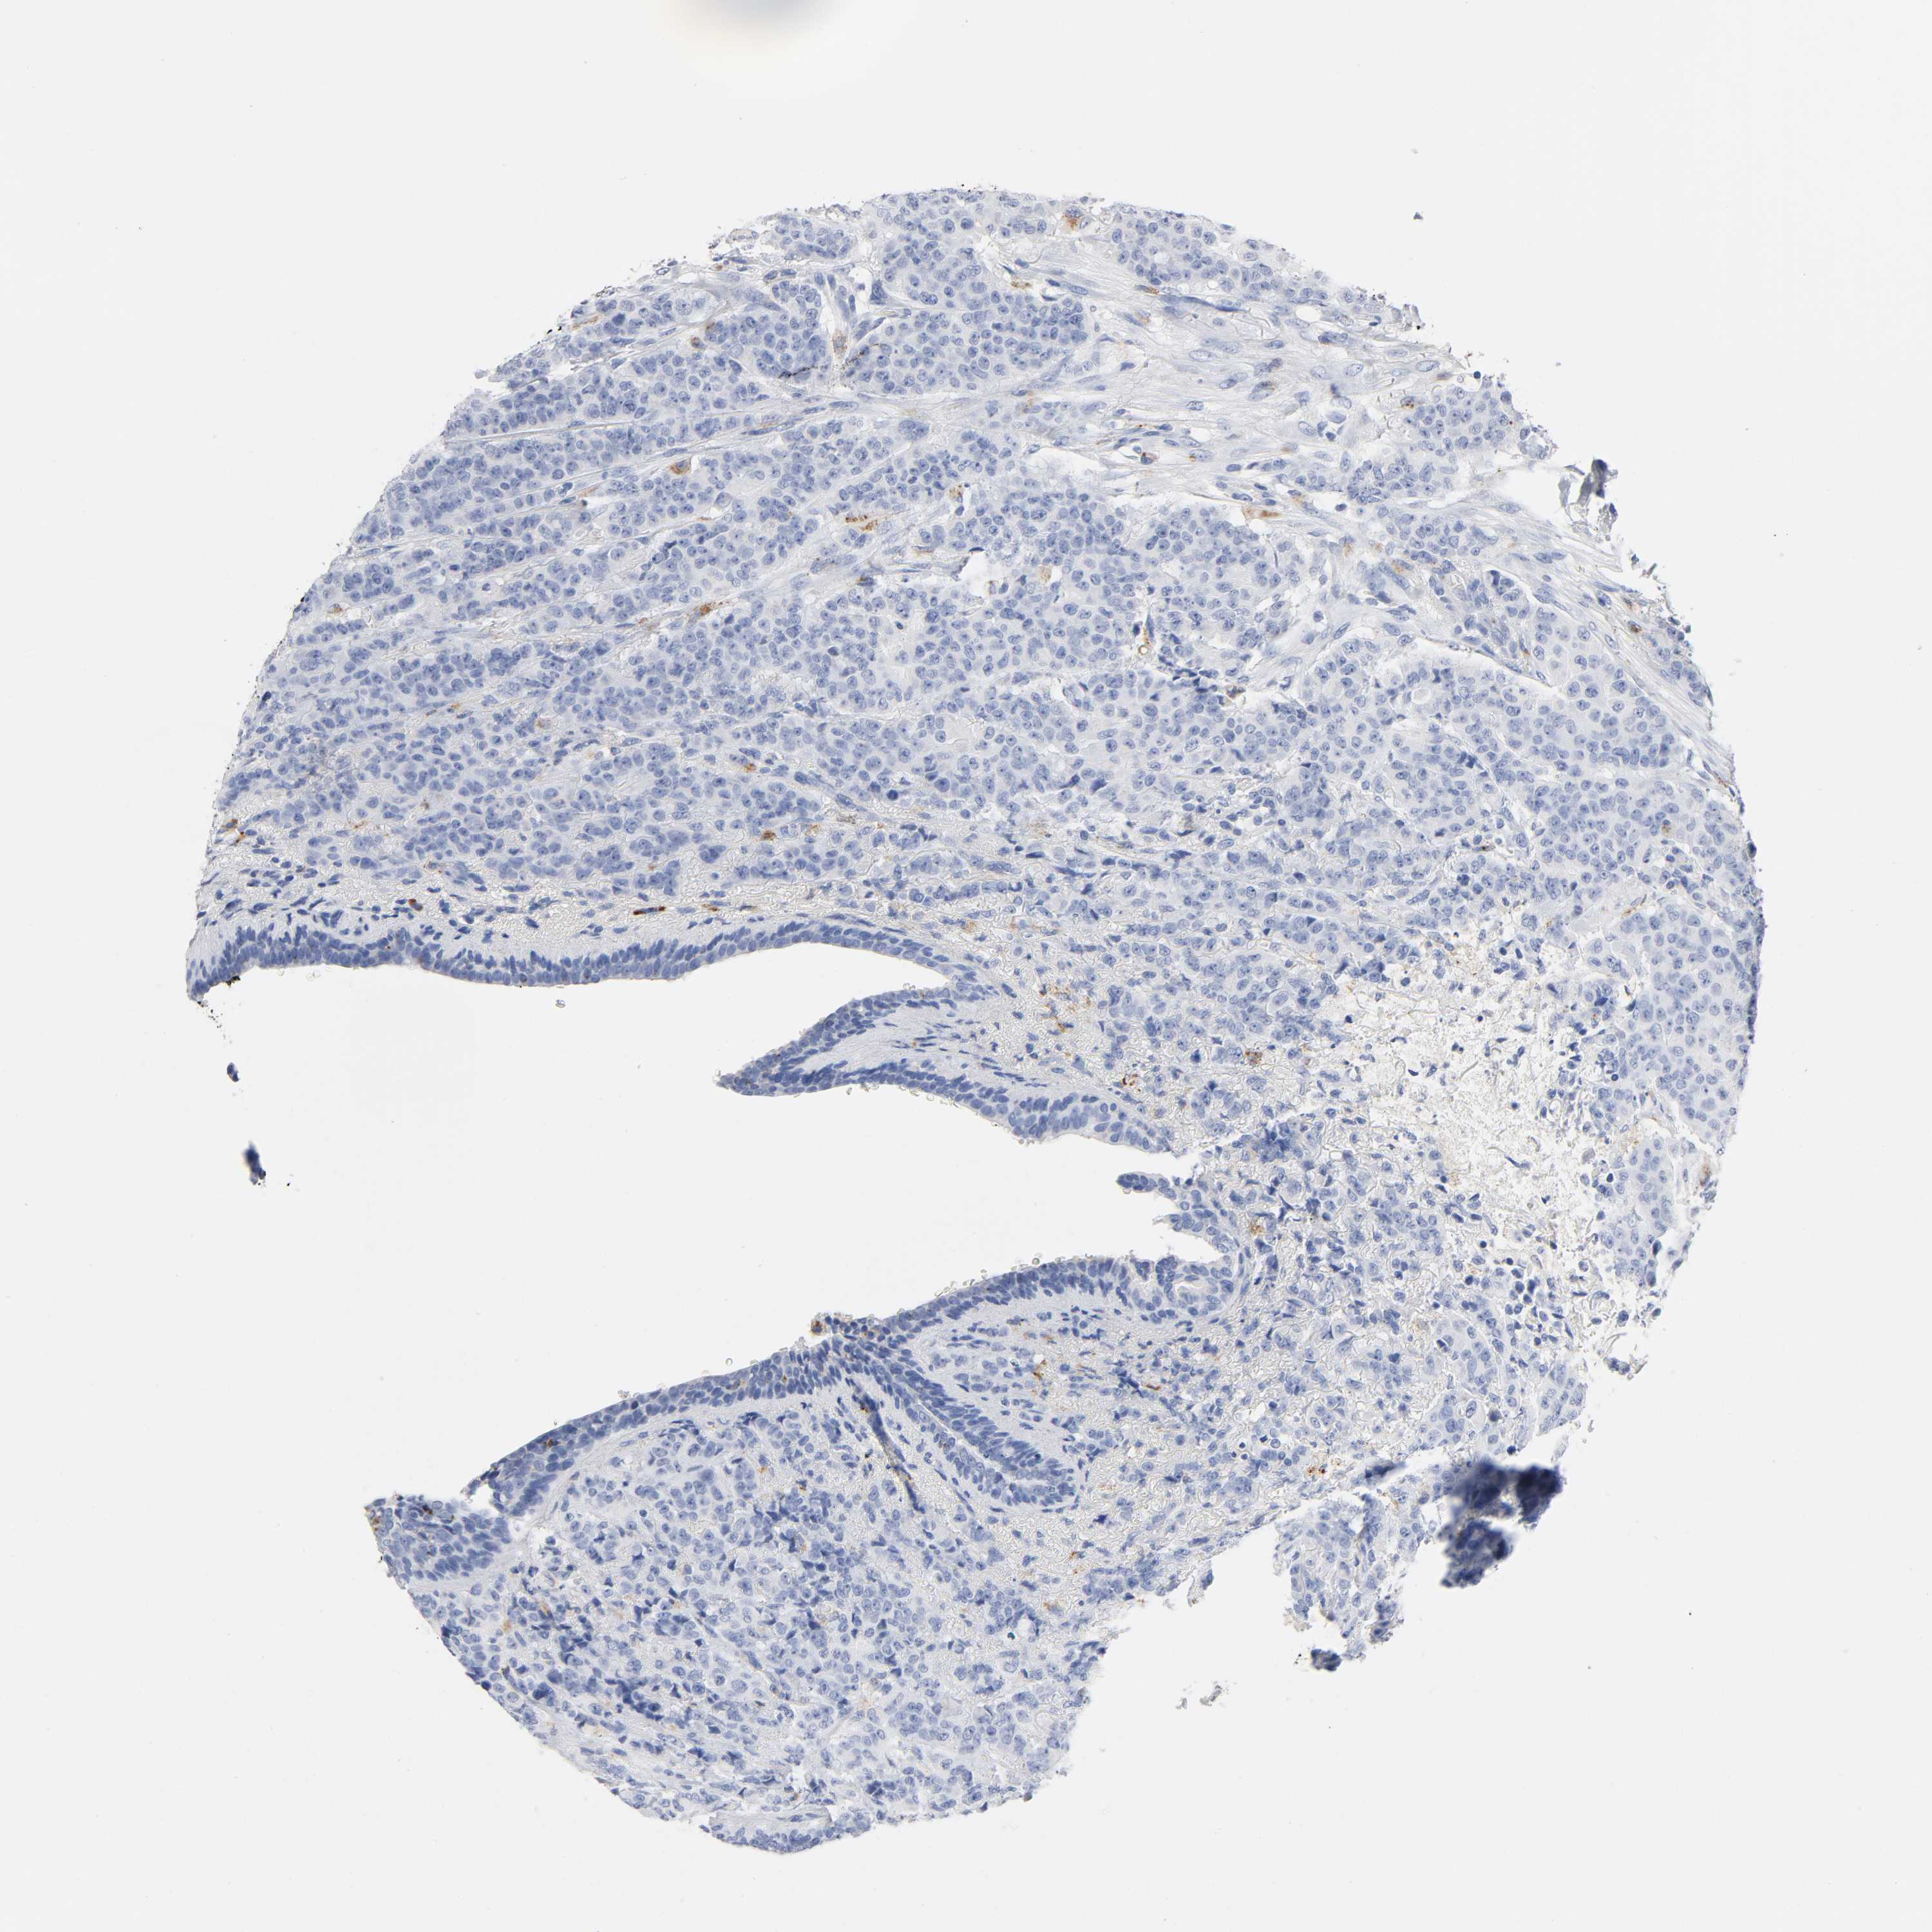

BRCA TCGA BRCA VALIDATION PROTEIN EXPRESSION

ANTIBODIES

AND

VALIDATION